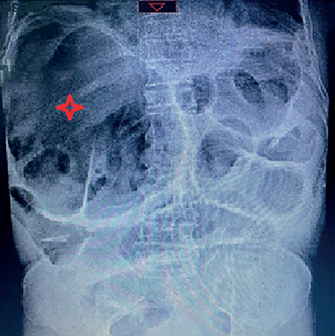

Ante el cuadro de obstrucción intestinal, se inició hidratación endovenosa y se pasó una sonda nasogástrica (SNG) que produjo 1000 ml de contenido fecaloide. Se tomó una serie de abdomen en la que se reportó aumento generalizado del contenido gaseoso intestinal, sin identificarse niveles hidroaéreos; llamaba la atención la sobre distensión de un asa presuntamente de intestino grueso sobre el ángulo hepático, con signo sugestivo del grano de café, además de la distensión de hasta 6 cm de asas intestinales delgadas proyectadas sobre el mesogastrio, con un patrón en pila de moneda y ausencia de gas distal (Figura 1).

Una radiografía simple de abdomen es el estudio de imagen inicial en los pacientes hemodinámicamente estables, sin embargo, es diagnóstica en menos del 20 % de los casos. Los tres signos típicos que pueden observarse en la radiografía son la dilatación del ciego, un nivel hidroaéreo único en el cuadrante inferior derecho y la ausencia de gas en el colon distal 7,9. En nuestro caso observamos ausencia de gas en el colon distal y una dilatación del colon hacia cuadrante superior derecho, que en el análisis retrospectivo probablemente se trataba del ciego dilatado.